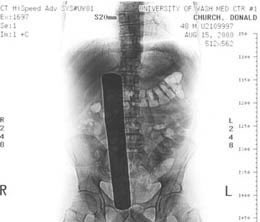

١.تم استئصال ورم في الجهة اليمنى من القولون لهذا المريض في المركز الطبي لجامعة واشنطن UWMC عام٢٠٠٢

بعد العملية بدأ بالشكوى من آلام بالبطن استمرت لمدة شهر، تم اكتشاف وجود malleable retractorنستخدمه عادة للمساعدة بإقفال الجرح، طوله ٣٣ سم!